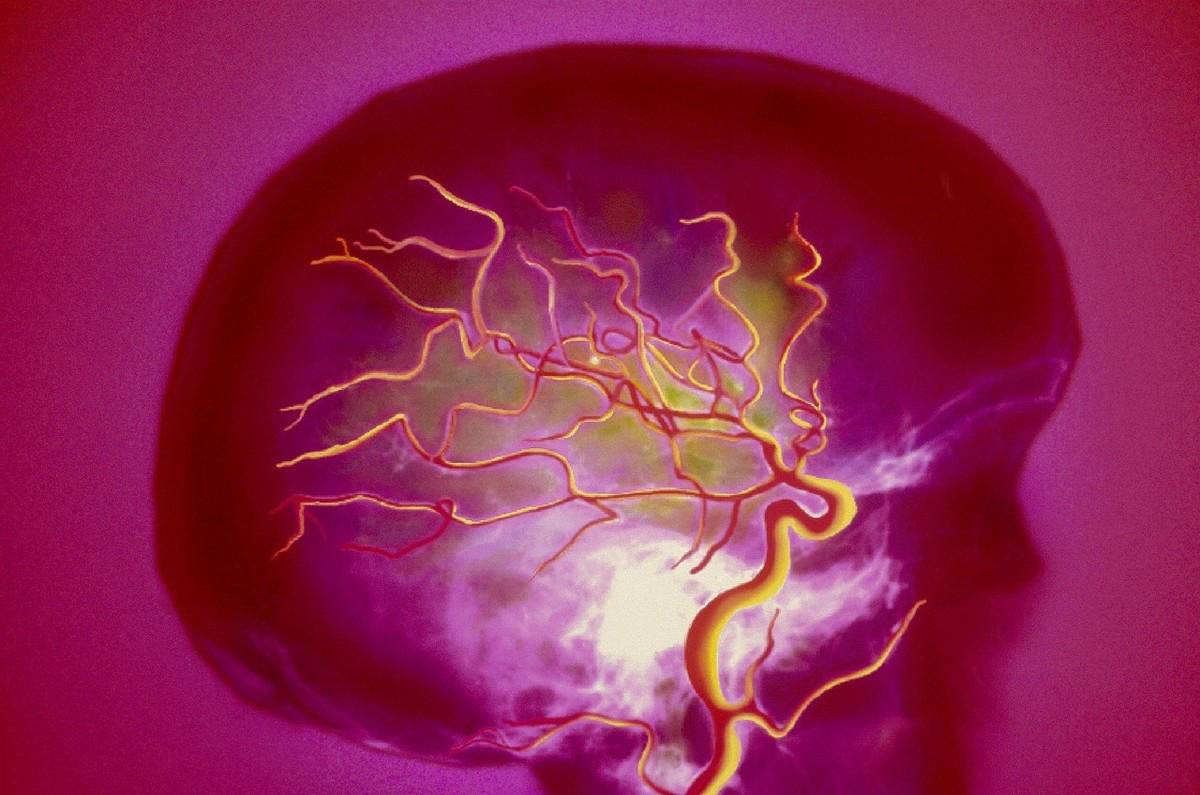

一、脑功能障碍

脑动脉硬化、脑供血不良、脑细胞衰退而影响生理功能。这多表现为微小动作的手抖,尤其写字时更为明显,多在一侧。粗活用力时的大动作,则不一定会发生颤抖。若某一血管梗塞,除手抖外,还会有相应的神经功能缺损,手抖的症状会随年龄的增加和血管硬化的加重而加重。